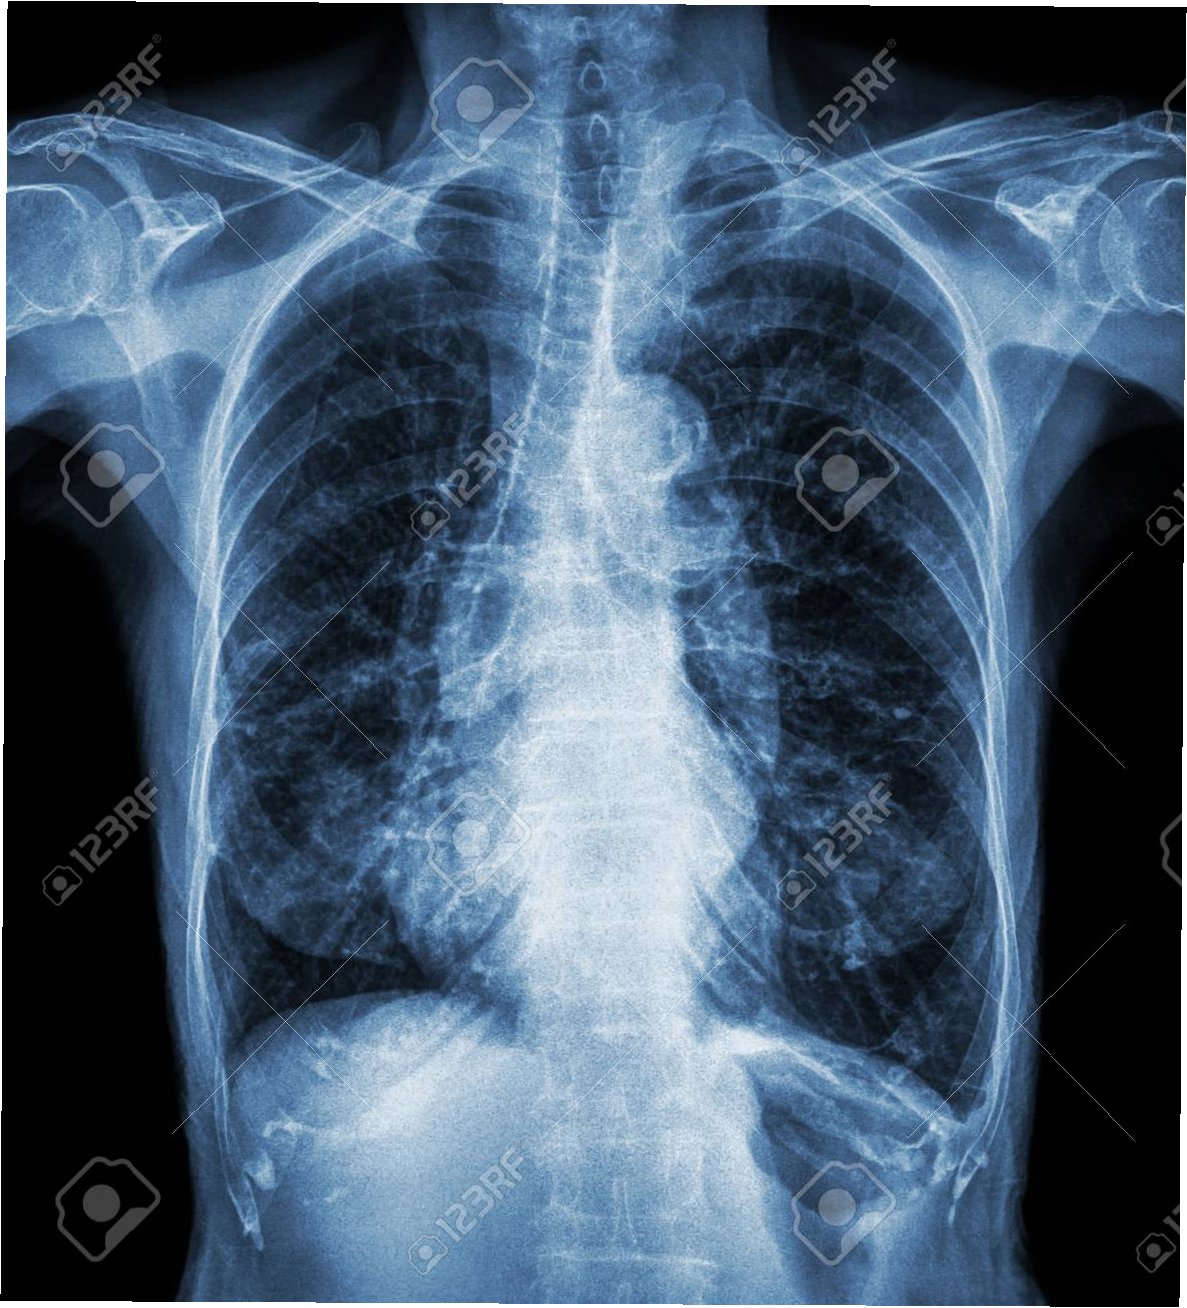

2019년부터 시작된 원인 불명의 밤마다 반복되는 고열로 병원을 찾은 사이먼스 씨는 CT 검사 결과 충격적인 사실을 마주했습니다. 사고 당시 폐 깊숙이 들어간 먼지 파편이 체외로 배출되지 못한 채 딱딱하게 굳어 왼쪽 폐 기관지를 완전히 막고 있었던 것입니다. 그는 “기계에 깔려 움직일 수 없을 때 먼지를 들이마셨는데, 그게 깊이 들어가 굳어버렸다”고 당시 상황을 설명했습니다. 의료진은 외상으로 인해 체내에 남은 이물질이 장기간에 걸쳐 칼슘으로 둘러싸여 석회화가 진행된 것으로 판단했습니다. 정밀 검사 결과, 좌측 폐는 5년간의 감염으로 기능을 완전히 상실한 상태였습니다.

의료진은 처음에는 석회화된 부분만 제거하려 했으나, 손상 범위가 너무 넓어 폐 전체를 적출해야 한다는 결론에 이르렀습니다. 사이먼스 씨는 결국 왼쪽 폐를 떼어내는 수술을 받았습니다. 그는 “작은 먼지 한 톨이 내 인생을 이렇게 바꿀 줄 몰랐다”며 “수술 동의서에 서명하던 순간이 인생에서 가장 무거웠다”고 심경을 토로했습니다. 이처럼 외상으로 체내에 남은 이물질은 장기간에 걸쳐 석회화되며 염증이나 조직 괴사를 일으킬 수 있습니다. 특히 폐 조직은 통증 수용체가 적어 초기 증상 인지가 어렵고, 뒤늦게 발견되는 경우가 많아 주의가 필요합니다.